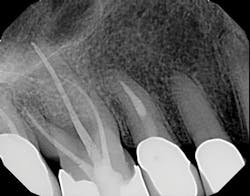

Figure 2

I then employ two instruments, the 30/02 Shaper and the 30/04 Finisher (Tango-Endo, EDS) that are also used in a 30- to 45-degree, reciprocating handpiece, but designed with a more efficient flute design to remove tissue and shave dentin away in the longer bucco-lingual isthmuses that may be present. These instruments are also highly resistant to separation, but for caution I suggest limiting their use to three teeth. Generally, there is little need to instrument the canals with larger instruments. If, in fact, the canal is wider than the instrument mesio-distally, in the same way the instruments can broaden the preparation bucco-lingually, they will also accomplish this task in the mesio-distal plane. Once shaped to these dimensions, the canal is properly sealed, flooding the canal with epoxy resin cement via a bidirectional, spiral applicator and the placement of a single Tango-Endo gutta-percha point. See figures 2 and 3 for before-and-after radiographs.